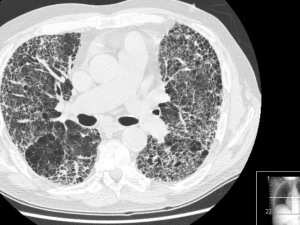

Localizan nuevos marcadores para el diagnóstico y pronóstico del cáncer de pulmón 27.02.2020 Científicos españoles han identificado algunas regiones repetitivas que en todos los pacientes y en todos los tipos de cáncer de pulmón estudiados tienen el mismo comportamiento